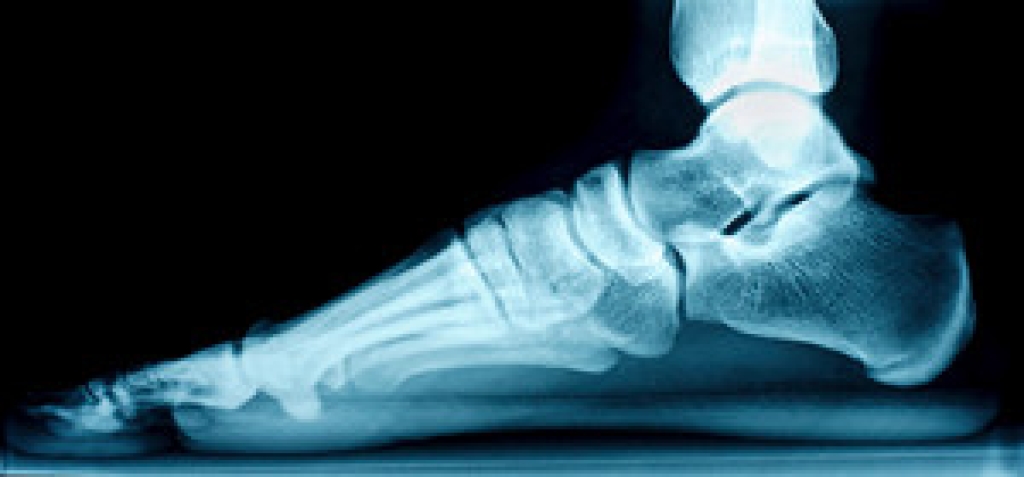

Plantar fasciitis is a common foot condition that may cause a stabbing pain in the heel. As a result, someone who has the condition may find common activities such as running and walking to be extremely painful. Plantar fasciitis occurs when there is an injury of the plantar fascia--the long structure at the base of the foot that connects the heel to the toes. Stretching has been proven to be effective in alleviating pain related to plantar fasciitis, so it is important that those with the condition incorporate stretching into their daily routines.

Plantar fasciitis is the inflammation of the thick band of tissue that runs along the bottom of your foot, known as the plantar fascia, and causes mild to severe heel pain.